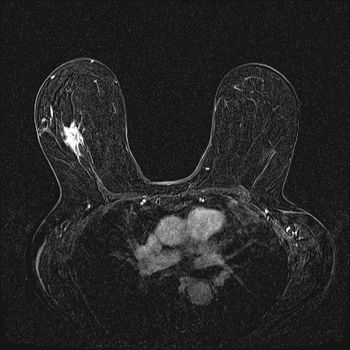

A 72 year-old woman presents for routine screening mammogram with no complaints.